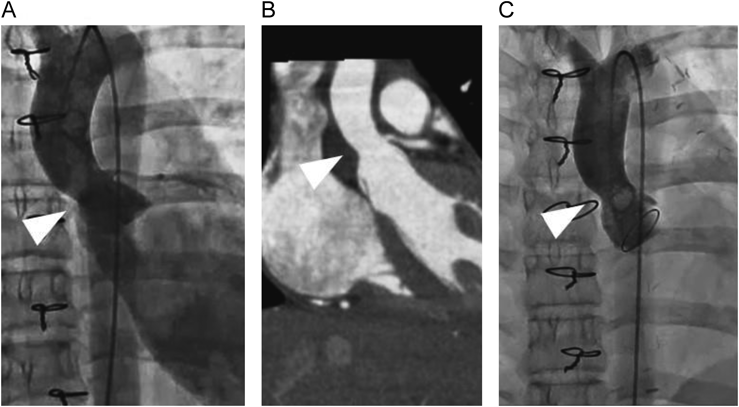

A 12-year-old girl with an anomalous origin of the left coronary artery from the right coronary cusp, characterized by intramural course of the coronary artery, underwent unroofing of the left main trunk. During the surgical procedure, aortic regurgitation (AR) emerged, prompting us to attempt commissural suspension and plasty to the right coronary cusp. Despite the aortic valve intervention included within a total cardiac arrest duration of 174 minutes, a trivial-mild degree of AR persisted. Subsequently, AR through the central and commissural regions between the left and the right coronary cusps progressively deteriorated (Fig. 1). The left ventricular end-diastolic diameter increased from 42 mm to 45 mm over a period of six months. Cardiac catheterization performed three months postoperatively revealed left ventricular end-diastolic pressure of 16 mmHg, AR being categorized as Sellers IV. Despite the absence of a discernible pressure gradient, morphological constriction was noted at the sino-tubular junction (Fig. 2A). Additionally, contrast-enhanced computed tomography confirmed the narrowing of the sino-tubular junction (Fig. 2B). Given the patient’s age and activity level, we considered AVNeo as a viable alternative to mechanical valve replacement.

Fig. 2 (A) Preoperative cardiac catheterization image. (B) Preoperative contrast enhanced computed tomography image. (C) Postoperative cardiac catheterization image. The white arrow heads denote the sino-tubular junction.

At the four-month postoperative assessment, cardiac catheterization revealed morphological constriction of the sino-tubular junction (Fig. 2C). On the other hand, trans-thoracic echocardiography did not indicate aortic stenosis; a peak velocity (Vmax) of 0.8 m/s and a mean pressure gradient (PG) of 2 mmHg.